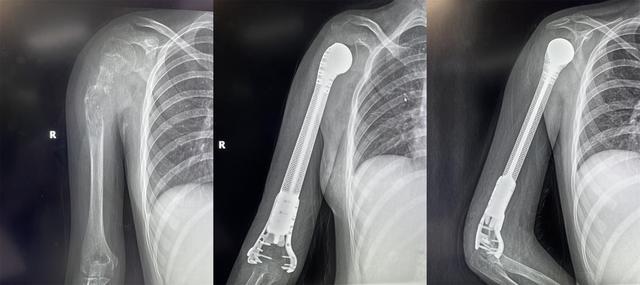

13歲少女患骨肉瘤面臨截肢,3D打印肱骨假體治療成功保肢

2022年4月19日,獲悉,西安市紅會醫(yī)院骨病腫瘤科為一名13歲小患者成功實施了肱骨惡性腫瘤切除3D打印假體重建術(shù)。165751qartxm1zze19w2ha.jpg

小欣(化名)因右肱骨中上段腫瘤,飽受疾病折磨,幾經(jīng)輾轉(zhuǎn)后來到西安市紅會醫(yī)院就醫(yī),活檢確診為 右肱骨中上段骨肉瘤 。

骨病腫瘤科楊團民主任介紹,骨肉瘤是一種好發(fā)于兒童長骨的骨端高度惡性的原發(fā)性腫瘤,治療原則為手術(shù)結(jié)合化療、放療綜合治療。 由于腫瘤范圍較大沒有生物重建可能,也沒有相關(guān)腫瘤假體,保肢難度很大,一直是業(yè)內(nèi)難題,所以普遍選擇截肢。 165751f8i13tpusqaqduut.jpg

對于一個13歲的女孩來說,截肢必然會對孩子的心靈帶來巨大陰影,同時小欣父母表達了強烈的保肢意愿后,最終決定選擇保肢方案。針對小欣的具體病情,骨病腫瘤科楊團民主任帶領(lǐng)團隊成員王志酬、黃桂林、邵宇雄、李爭爭主治醫(yī)師等人,經(jīng)過認真病例討論,決定 新輔助化療后,手術(shù)切除右肱骨骨腫瘤 。發(fā)揮3D打印在骨科領(lǐng)域優(yōu)勢,設(shè)計個體化3D打印肱骨上段鈦合金假體,結(jié)合人工肩關(guān)節(jié)技術(shù),保留部分正常骨、患肢長度,可實現(xiàn)肱骨重建。165751kg0sm7xwzxmksk7w.jpg

術(shù)前,經(jīng)精密計算機輔助設(shè)計、影像學數(shù)據(jù)鏡像反求和鈦合金3D打印,假體的3D打印仿骨小梁端和截骨端可以完美貼合,使骨長入得以實現(xiàn),達到生物重建效果。這樣既保留了關(guān)節(jié),也減少假體松動的發(fā)生率。同時空隙結(jié)構(gòu)利于軟組織長入。手術(shù)當日,在麻醉科配合下,楊團民主任團隊密切協(xié)作、精細操作,依次完成腫瘤切除、3D打印假體植入、軟組織重建系列操作。歷時3小時,順利完成醫(yī)院首例3D打印肱骨假體治療肱骨骨肉瘤手術(shù)。

目前,小欣全身狀況良好,正在進行積極的功能鍛煉,力爭盡早實現(xiàn)正常生活。